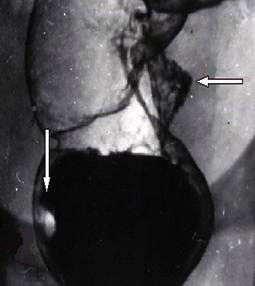

Рак толстой кишки.

Рис. 1. Блюдцеобразный рак среднеампулярного отдела прямой кишки (горизонтальная стрелка). «Пограничный» полип нижнеампулярного отдела (вертикальная стрелка).

Предоставил Дементьев Е.З.

Радиология-практика 2004 2: 48-56